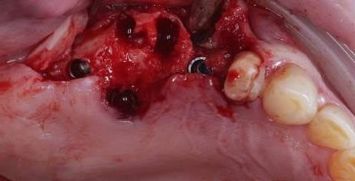

ОДНОМОМЕНТНАЯ ИМПЛАНТАЦИЯ

Удаление зуба 26. Установка имплантатов VEGA+ в позиции 25 и 27.

✔️ В позицию зуба 27 установлен VEGA+ RV 4.6x10 mm. Получена первичная стабильность 20 Н/см. Установлен винт-заглушка

✔️В позицию зуба 25 установлен VEGA+ RV 4.1x14 mm. Получена первичная стабильность 50 Н/см. Установлен винт-заглушка.